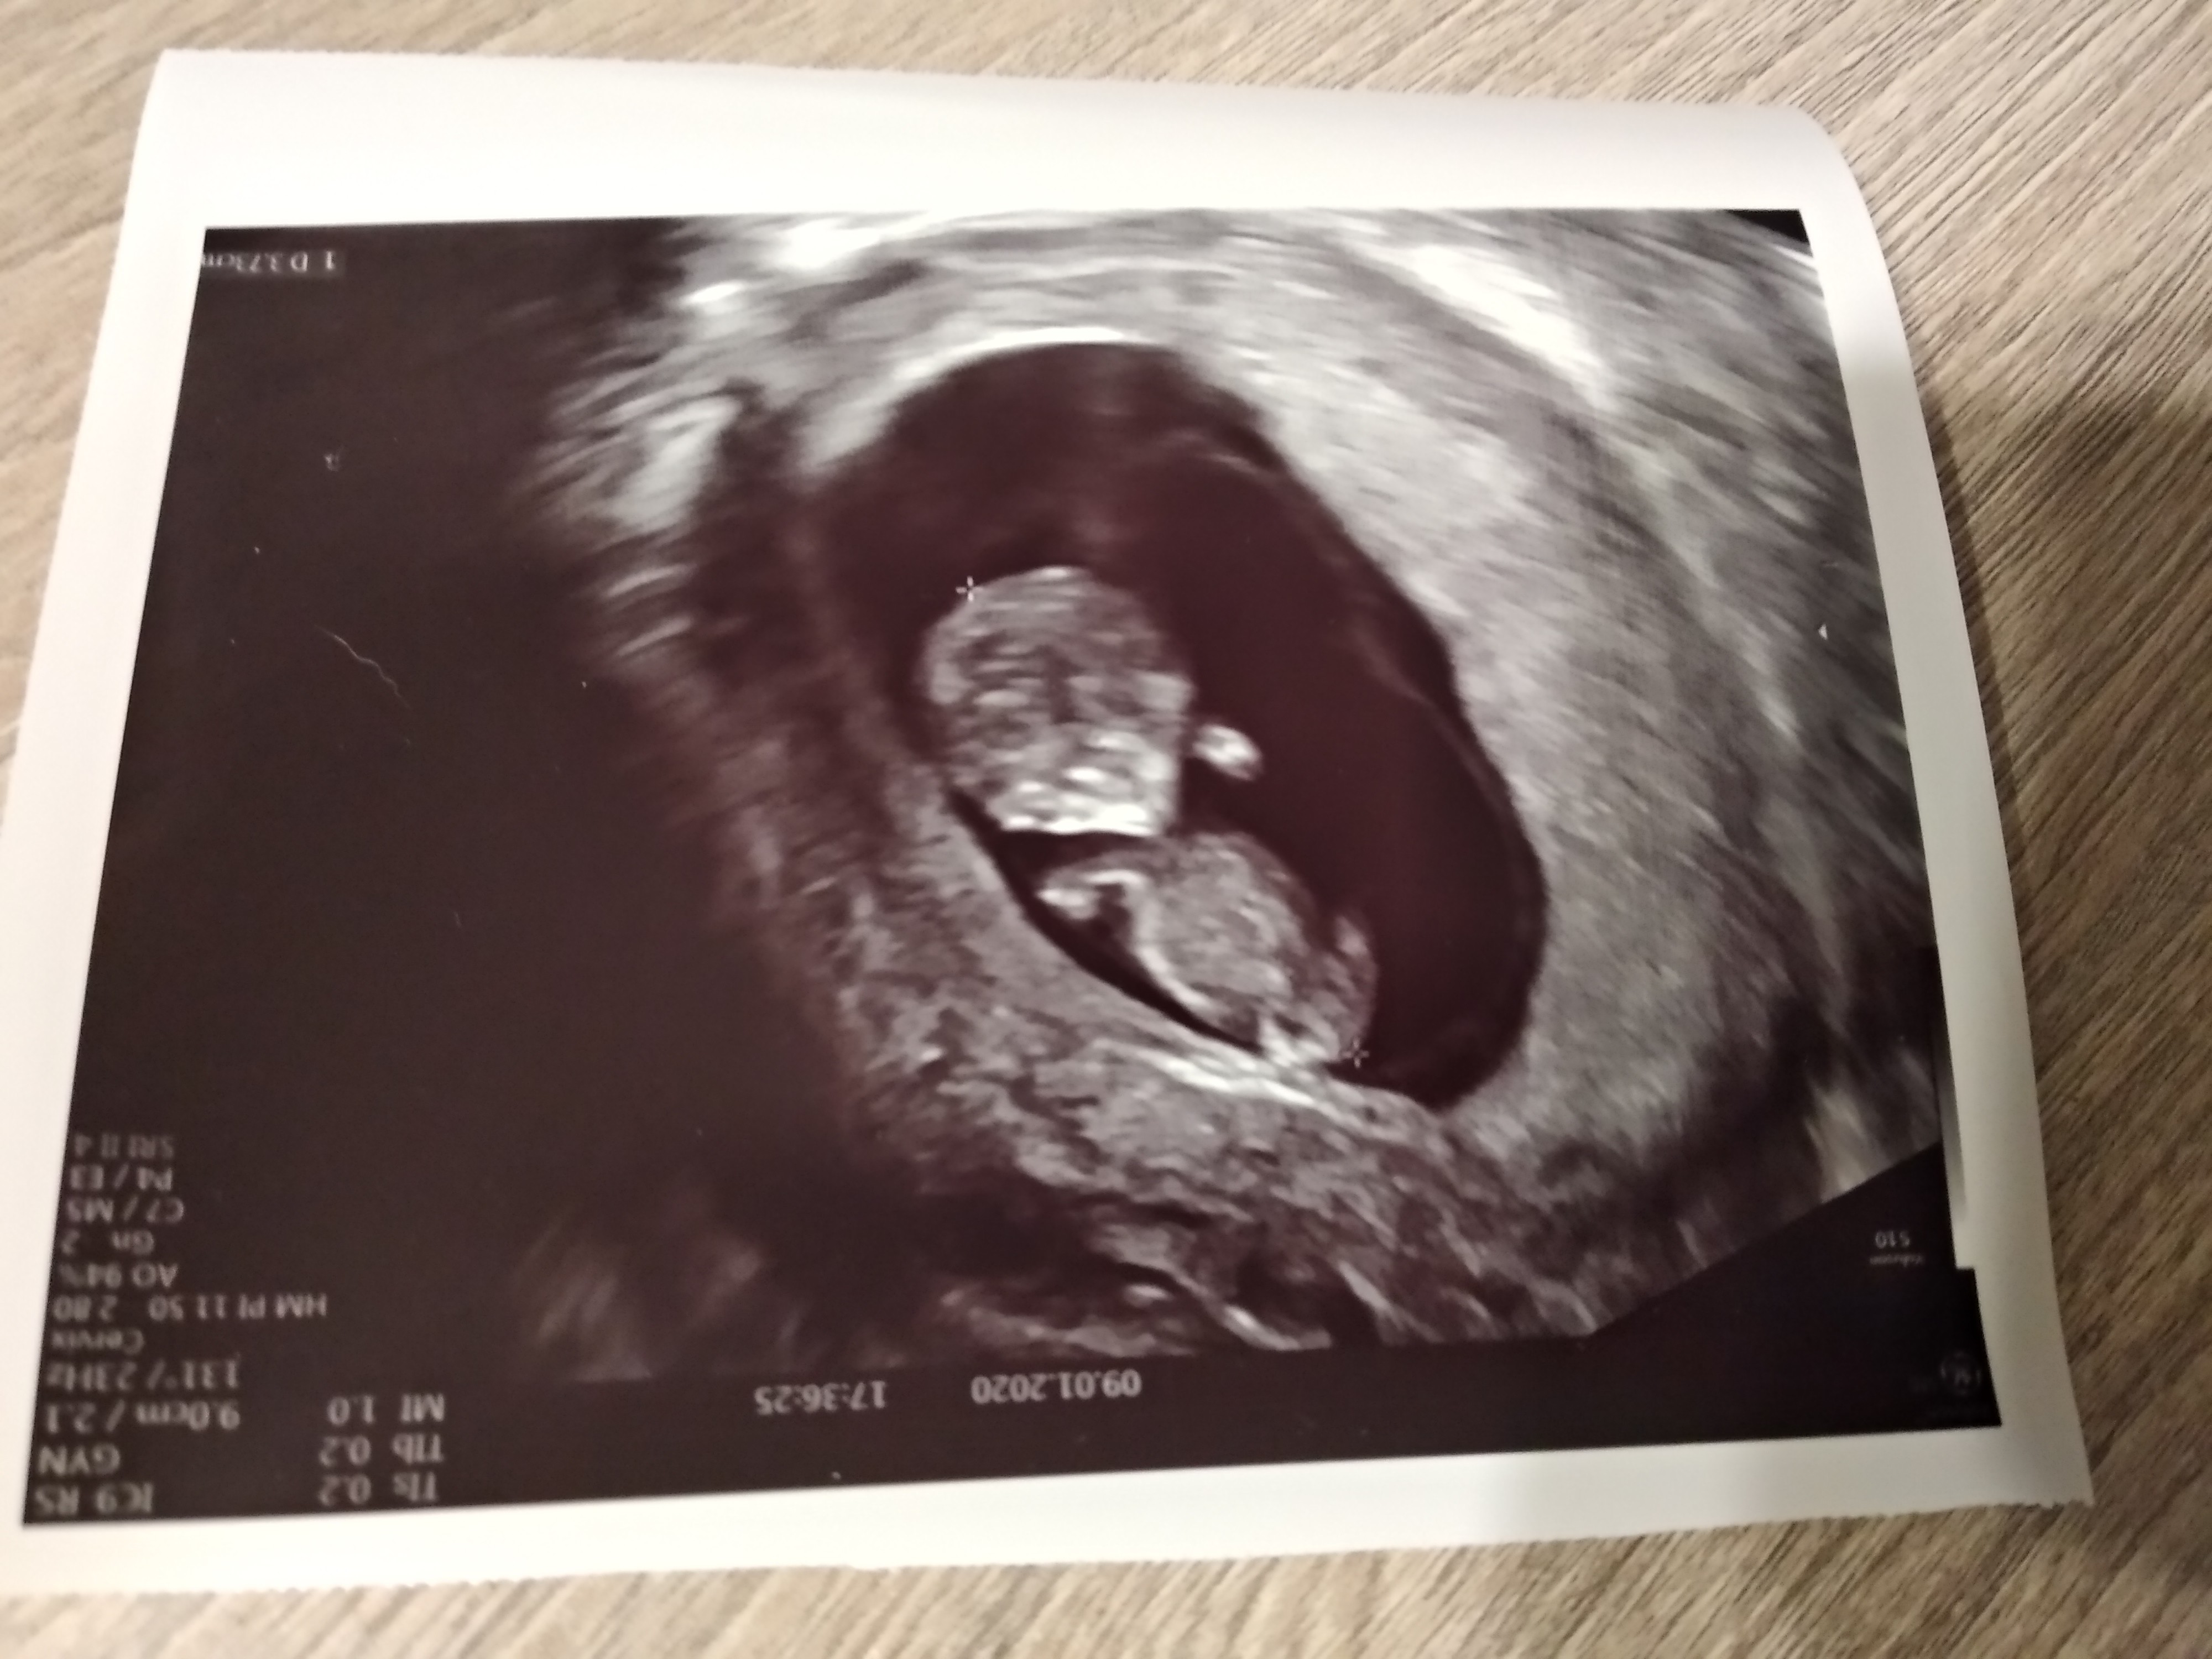

Ja już po wizycie. Wszystko wporzadku. Serducho bije, dzidzia ma już prawie 4 cm. [emoji7]

Przytyłam aż 100 gram także widać że mdłości były okrutne. Teraz mam zamiar nadrabiać [emoji16]

Zobacz załącznik 1066251